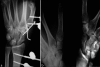

(a) Postoperative radiograph showing the fixation with K-wires and a mini fixator (b) radiographs at 1-year follow-up showing healed fracture with congruent joints